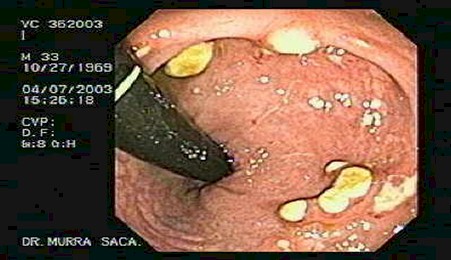

Se observa el recto en retroflexión, observándose múltiples lesiones en “botón de camisa”